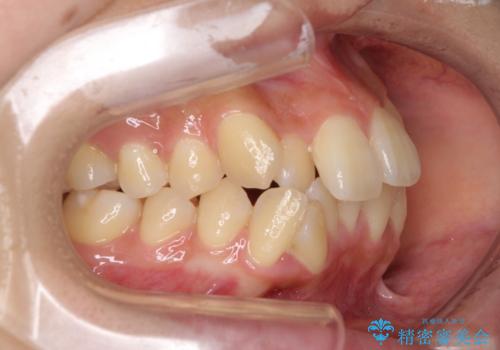

- 前歯のデコボコやクロスバイトと上顎の前突感による口の閉じにくさを気にして来院された患者様です。

目立たない装置を希望されたので、上顎が裏側装置のハーフリンガルを選択し、上下左右の小臼歯(計4歯)を抜歯して矯正治療を行うこととしました。

表側のワイヤー矯正に比べると治療期間は長く、費用も高額となりますが、どうしても目立たせたくないという方にはお勧めの抜歯矯正です。